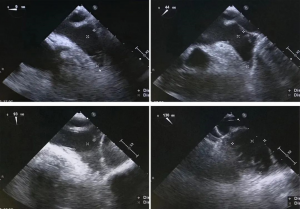

经食道超声检查显示,左房及心耳内未见血栓征象;CDFI提示左心耳血流充盈可,流速约0.52 m/s;左心耳形态呈鸡翅型,梳状肌发达;房间隔完整,未见卵圆孔未闭;升主动脉未见斑块形成。结合评估结果和患者及家属意愿,参考指南推荐后决定行“一站式”左心耳封堵+导管消融手术。

术前TEE检测

术中经股静脉路径,在房间隔穿刺后,成功将导丝送入左心房,进入左上肺静脉,沿导丝通路送入Lefort导引鞘管后,将猪尾导管送入左心耳,随后进行左心耳造影,造影结果显示,左心耳深度足够,左心耳口部直径约23 mm,与术前TEE测量结果无显著差异,综合造影及TEE检查结果,为患者植入30 mm的Lefort左心耳封堵器。